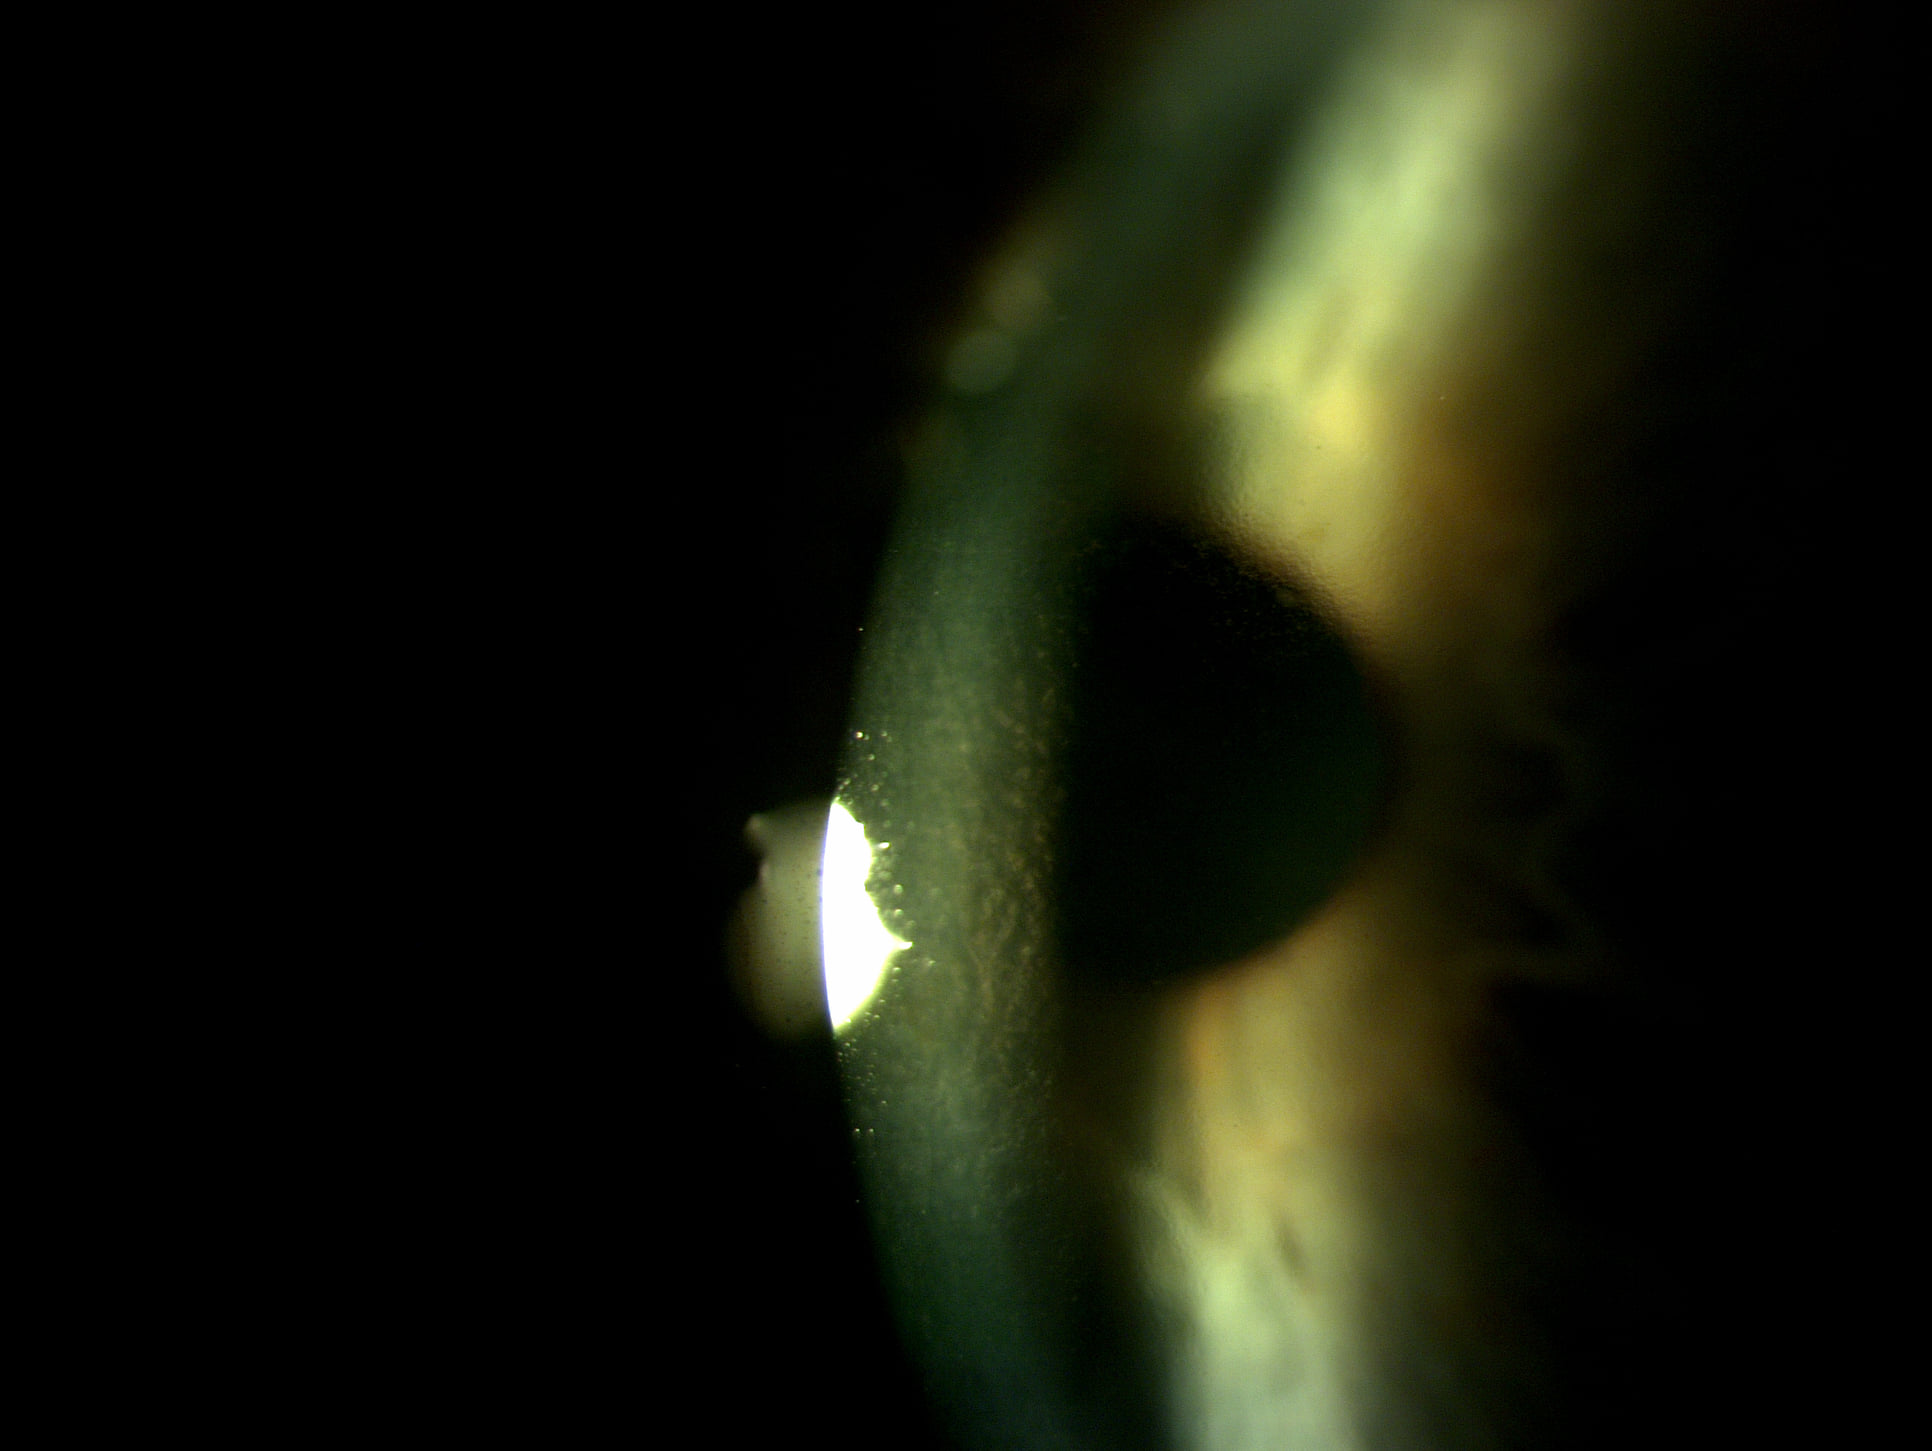

Mai jos, fotografii ale mai multor pacienti de-ai nostri cu Corneea Guttatta în faze medii, sau chiar avansate, la care am efectuat doar operația de cataractă, în urma căreia corneea a „supraviețuit” cu brio și nu a mai fost nevoie – cel puțin până acum – de un trasplant de cornee.